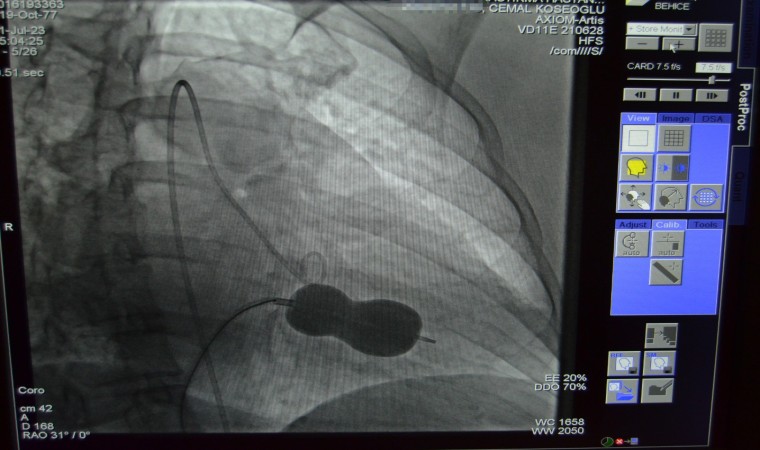

ALANYA'da ilki gerçekleştirilen bu işlem hakkında konuşan ALKÜ Tıp Fakültesi Öğretim Üyesi Doç. Dr. Cemal Köseoğlu, "Hastanemizde ilk kez uygulanan bu işlemi kardiyoloji birimi hekimleri olarak birlikte değerlendirdik ve mitral balon yardımıyla işlemi yapma kararı aldık. Hastamız Behice Hanımı, Anjiyo ünitemizde hiç uyutmadan mitral balon yardımıyla kasıktan girerek daralmış kapağını bir buçuk saat süren işlem sonunda açtık. Son kontrollerimizi yaptık. Hastanın kalp kapağı gayet güzel çalışıyor. 2 gün yoğun bakımda takibi sonunda taburcu işlemlerini gerçekleştireceğiz" dedi. Ayrıca, tıp teknolojisinin gelişimi ve ameliyatsız müdahale olanaklarının artmasıyla ciddi kapak müdahalelerini düşük risklerle gerçekleştirme şansları bulunduğunu da vurguladı.

Alanya Eğitim ve Araştırma Hastanesi'nde, romatizmal mitral darlığı ve kalbin sağ tarafında büyüme teşhisi konulan Behice Kanmaz'a, hastanede ilk kez gerçekleştirilen ameliyatsız bir işlemle yardım edildi. Alanya'da yaşayan 45 yaşındaki hastanın nefes darlığı ve çarpıntı şikayetleri üzerine Alanya Eğitim ve Araştırma Hastanesi'ne başvurdu. Yapılan ayrıntılı tetkikler sonucunda romatizmal mitral darlığı ve kalbin sağ tarafında büyüme teşhisi konuldu. Kardiyoloji uzmanları, hastanın mitral darlığını ameliyatsız bir işlemle tedavi etmeye karar verdiler.